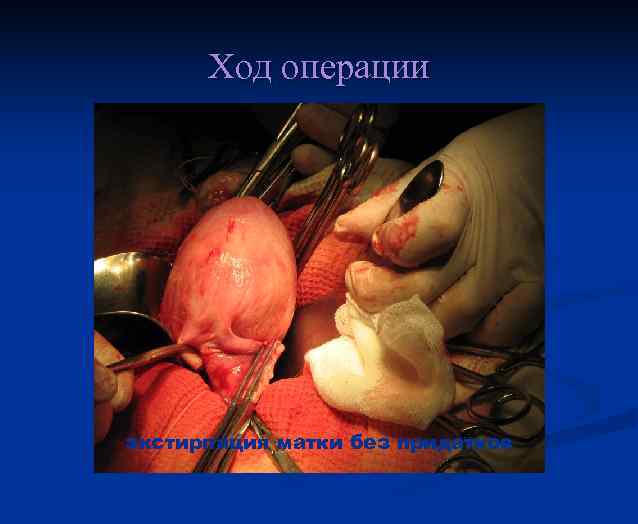

ОПЕРАЦИЯ Лапаротомия. Экстирпация матки без придатков.

Ход операции Лапаротомия

Ход операции экстирпация матки без придатков